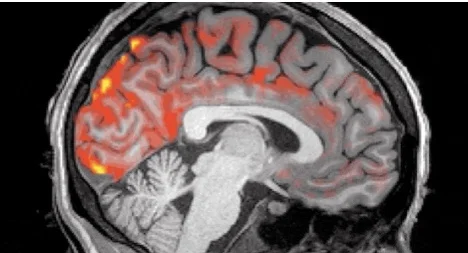

Tijdens de nacht geven we onze hersenen vrij letterlijk een wasbeurt. Golven van waterige cerebrospinale vloeistof (CSF) stromen over onze hersenen, pulseren ritmisch terwijl we dutten, en verwijderen tegelijkertijd alle afval en gifstoffen die zich niet in ons hoofd zouden moeten ophopen.

Het is al een tijdje bekend dat er deze elektrische activiteitsgolven in de neuronen zijn, maar tot nu toe was het niet bekend dat er ook golven in de CSF zijn. CSF is belangrijk voor het verwijderen van afval in de hersenen, maar tot nu toe waren wetenschappers nog niet op de hoogte van deze pulserende actie (laat staan dat we deze konden waarnemen).

In combinatie met de trage hersenactiviteit (die deels bedoeld is om onze herinneringen op hun plaats te fixeren) en de afname van de bloedstroom die plaatsvindt terwijl we slapen, lijken deze CSF-golven onnodige eiwitten en ander overbodig afval uit te wassen. Naarmate we ouder worden daalt echter de frequentie van de langzame hersengolf, dit nieuwe inzicht kan helpen bij onderzoek naar normale leeftijdsgerelateerde problemen, samen met specifieke aandoeningen.

We are quite literally having our brains washed every night. Waves of watery cerebrospinal fluid (CSF) flow over our brains, pulsing rhythmically while we are snoozing, and at the same time clearing out any debris and toxins that should not be building up inside our heads.

It has been known for a while that there are these electrical waves of activity in the neurons, but before now it wasn't known that there are waves in the CSF too. CSF is important for waste removal in the brain, but until now scientists had not known about this pulsing action (let alone been able to observe it).

In combination with the slow-wave brain activity (which is partly for fixing our memories in place) and the decrease in blood flow that happens while we sleep, these CSF waves look to be washing out unnecessary proteins and other redundant debris. As slow brain wave frequency drops as we get older, this new understanding could help with research into normal age-related problems, along with specific disorders.